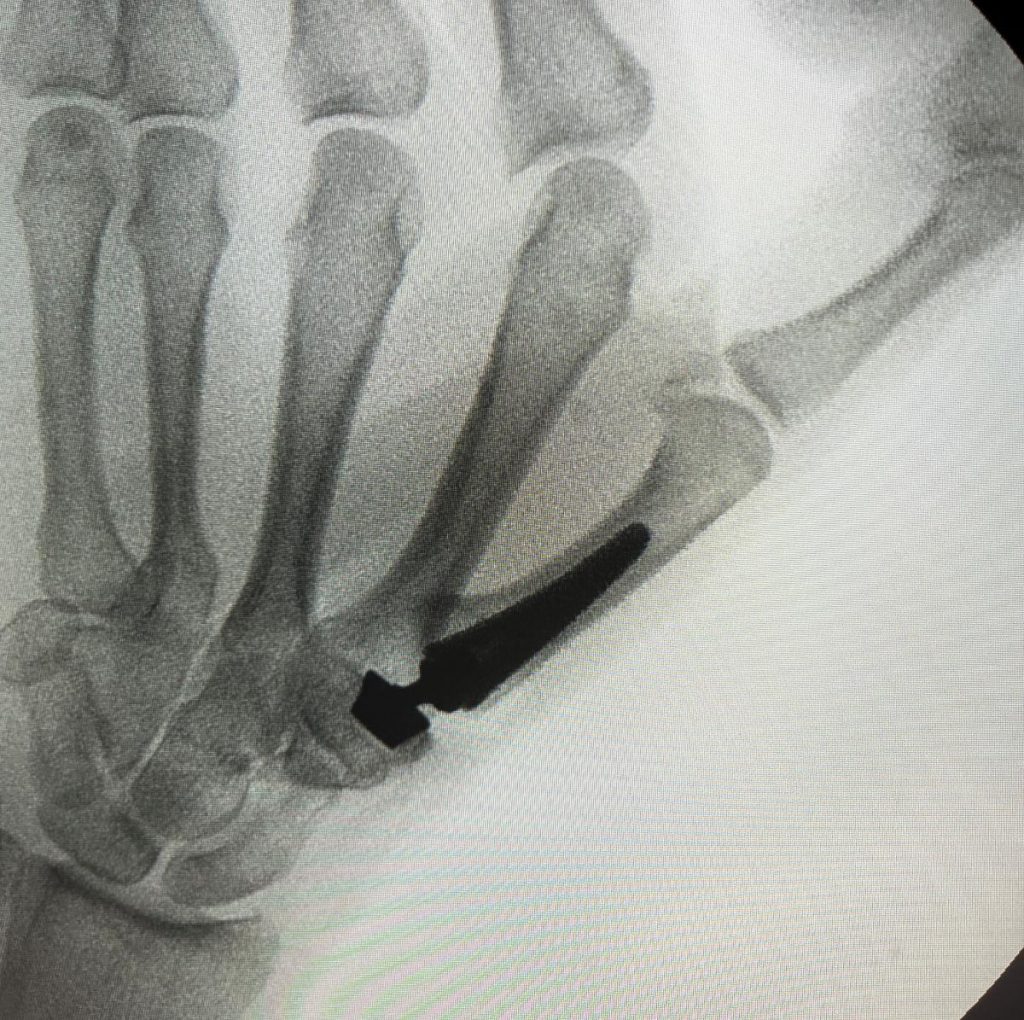

Los pacientes que no responden a tratamiento conservador pueden necesitar cirugía.  Están descritas diferentes técnicas para tratar la Rizartrosis.  Entre las más utilizadas están las prótesis (Figuras 3 y 4), que permiten una recuperación funcional rápida con una muy buena respuesta al dolor.  El Dr. Polo le informará de cuál es la opción más adecuada a su caso.

RIZARTROSIS Figura 3 - Prótesis de articulación TMC por rizartrosis AP

Figura 3 - Prótesis de articulación TMC por rizartrosis AP